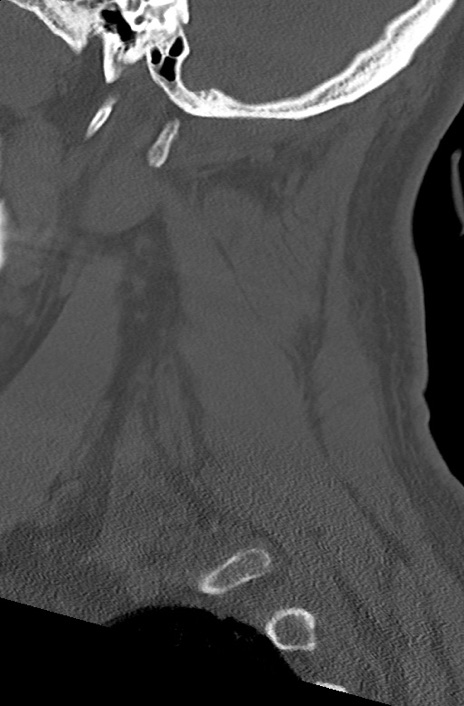

頚椎CT

矢状断像と横断像